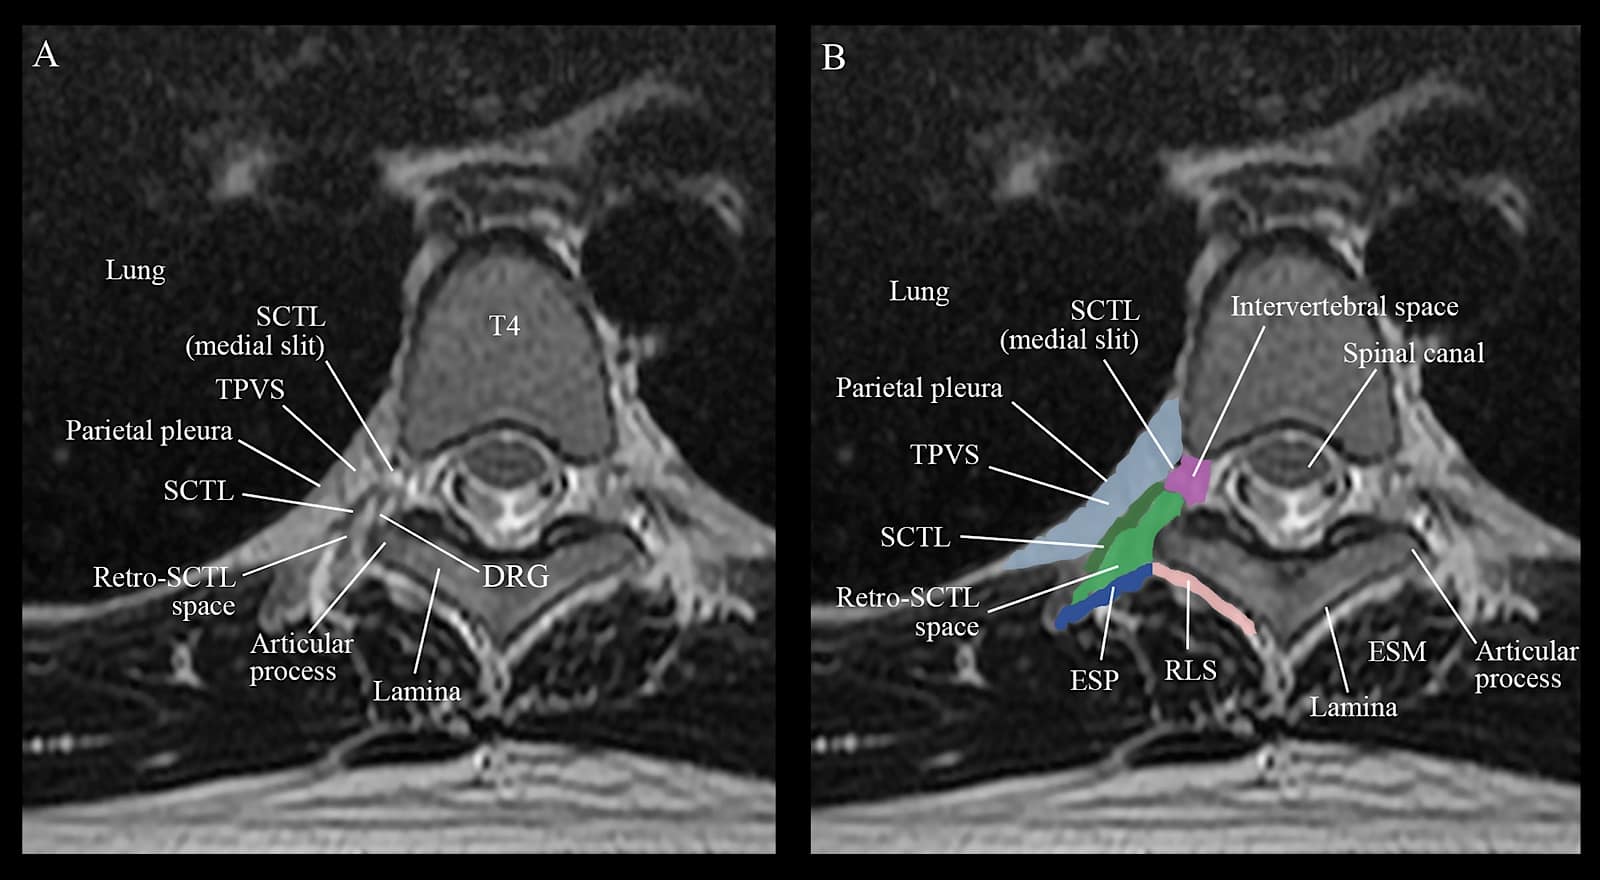

Figure 6. (A) Axial (transverse) MRI of the thoracic paravertebral region from the level of the T4 vertebral body and inferior articular process corresponding to the level at which the authors perform ultrasound-guided thoracic paravertebral block. Note the clear depiction of the superior costotransverse ligament (SCTL), retro-SCTL space, and the potential communications between the fascial planes behind the intertransverse tissue complex and the thoracic paravertebral space (TPVS). Two images of the same MRI are presented, with no color highlights (A) and with color (B) highlights assigned to various anatomic structures and tissue planes for clarity and comparison, using Adobe Photoshop (Adobe, San Jose, California, USA). Note the anatomic relationship of the retro-SCTL space to the ESP (erector spinae plane), retrolaminar space (RLS), TPVS, and the intervertebral space (foramen). DRG represents dorsal root ganglion; ESM, and erector spinae muscle.

SCTL = superior costotransverse ligament, TPVS = thoracic paravertebral space, ESP = erector spinae plane, RLS = retrolaminar space, DRG = dorsal root ganglion, ESM = erector spinae muscle

Reproduced with permission from the Department of Anesthesia and Intensive Care, The Chinese University of Hong Kong, Faculty of Medicine, www.aic.cuhk.edu.hk/usgraweb.

The TPVS is continuous with the contiguous space above and below,34 the epidural space medially via the intervertebral foramen,35 the intercostal space laterally; and the contralateral TPVS via the epidural and prevertebral space (Figure 1-3.).34 Communication with the contiguous paravertebral spaces above and below occurs not only via the paravertebral space,34 but also via the costotransverse space.36-38 The anatomy of the TPVS has recently been redefined with the characterization of the SCTL and identification of the “retro-SCTL space” (Figures 5 and 6), using three-dimensional micro-CT imaging of paravertebral tissue specimens in cadavers.36 Contrary to previous understanding,1 the SCTL forms an incomplete posterior wall of the TPVS with the lateral and medial slits (see Figures 3 and 5).29,39 The former lies laterally between the IICM and the SCTL while the latter lies medially between the SCTL and the vertebral body (Figures 3 and 5).29,39 The costotransverse space, located between the neck of the rib and the transverse process, is filled with fat and loose connective tissue and is visible as a distinct anatomical space in micro-CT images.36 The retro-SCTL space36 also filled with fat, and connective tissue communicates with the erector spinae and retrolaminar planes posteriorly, TPVS anteriorly via the lateral and medial slits in the SCTL,29 intervertebral canal and epidural space medially,37 the intercostal space laterally via the lateral slit in the SCTL (Figures 5 and 6), and with the contiguous TPVS and retro-SCTL space above and below via the costotransverse space.36,37 The location of the costotransverse foramen within this redefined paravertebral anatomy is unclear. However, it might represent the medial end of the retro-SCTL space as depicted in Figures 5 and 6,29,37 given its proximity to the base of the transverse process and inferior articular process (IAP).

The Retro-SCTL Space and Its Role in Thoracic Anesthesia and Analgesia

Given the unique anatomy of the retro-SCTL space and its communications with the adjoining paraspinal fascial planes, TPVS, and neuraxis (described above),36,37 we believe it is an important crossroad for LA spread for the intertransverse process blocks (ITPB) or injections behind the ITTC.29,57 The presence of the ventral and dorsal rami of the thoracic spinal nerve, and the dorsal root ganglion within the medial aspect of the retro-SCTL space (Figures 5 and 6),36,37 also indicate that it may be possible to produce anesthesia and or analgesia of the ipsilateral hemithorax by injecting the LA behind the SCTL or ITTC.29,30 This is the proposed anatomic basis for an ITPB29,57 that has recently been described as an effective and potentially safer alternative to avoid pleural puncture30,31,58 than a TPVB. A detailed description of how an ITPB may affect the ventral and dorsal rami of the thoracic spinal nerve to produce anesthesia and/or analgesia of the ipsilateral hemithorax is beyond the scope of this article and discussed elsewhere.29